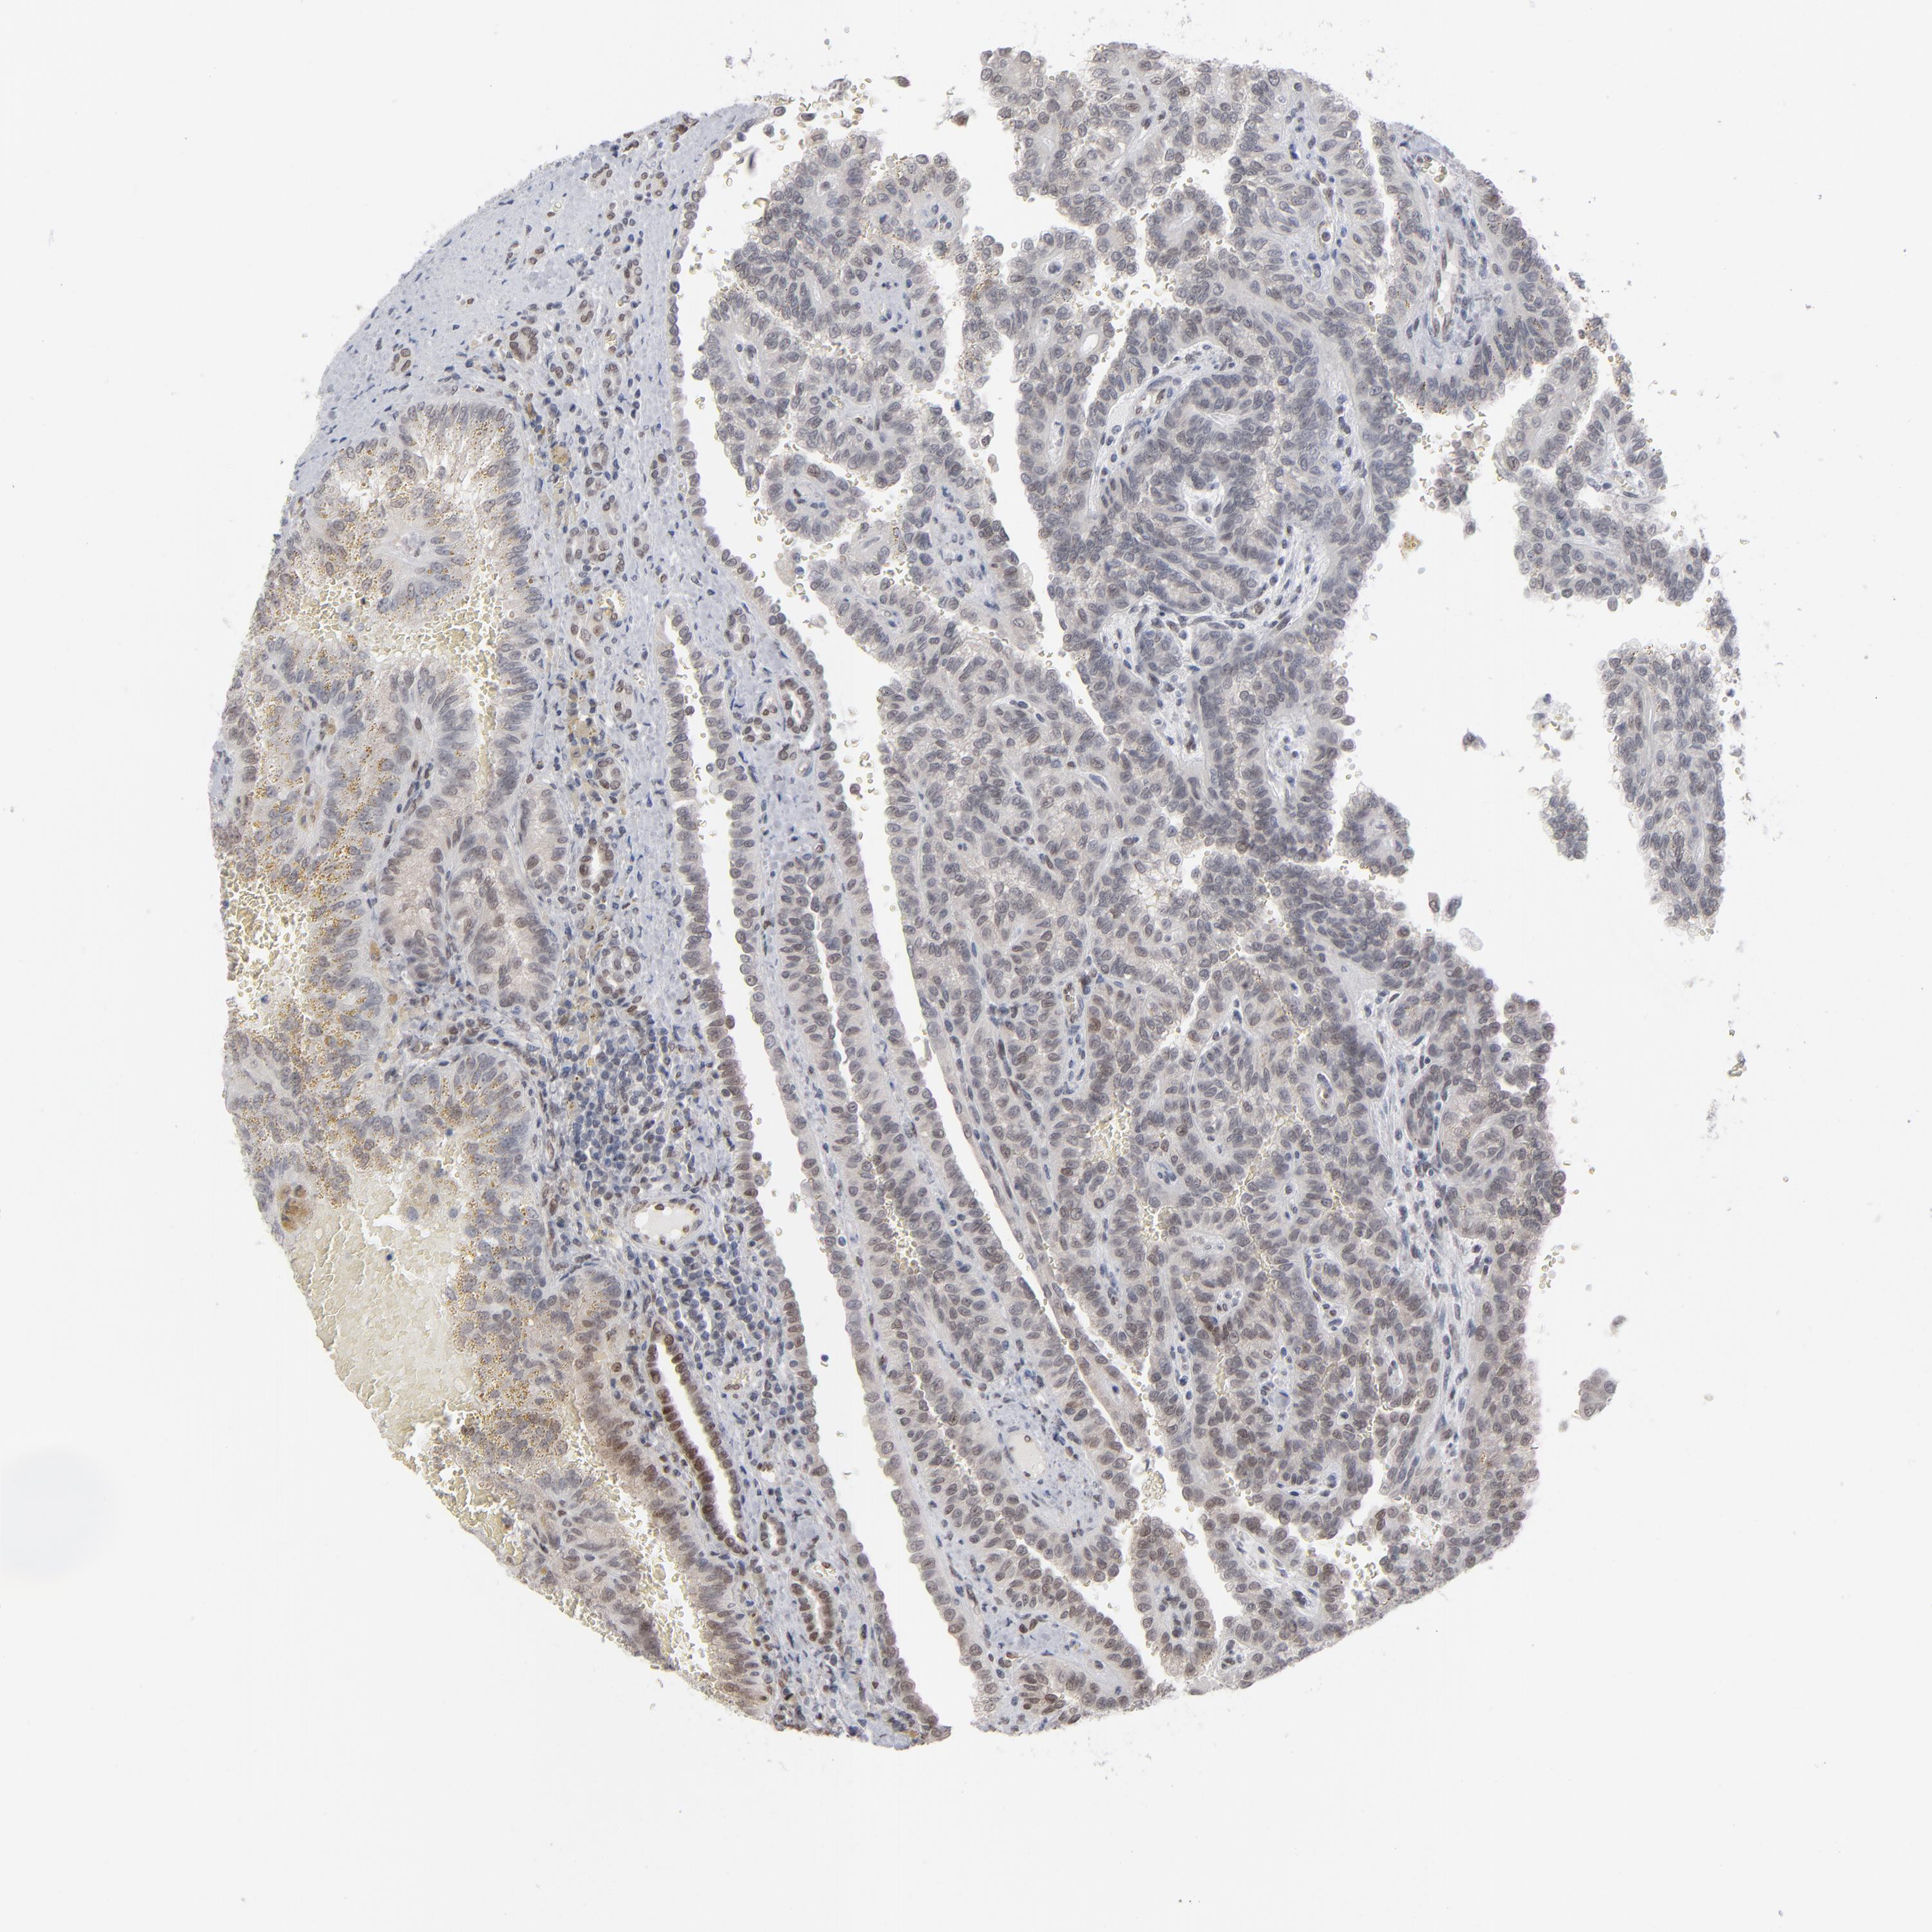

KIDNEY RENAL CLEAR CELL CARCINOMA (VALIDATION) - Interactive survival scatter ploti

The Survival Scatter plot shows the clinical status (i.e. dead or alive) for all individuals in the patient cohort, based on the same data that underlies the corresponding Kaplan-Meier plots. Patients that are alive at last time for follow-up are shown in blue and patients who have died during the study are shown in red.

The x-axis shows the expression levels (FPKM) of the investigated gene in the tumor tissue at the time of diagnosis. The y-axis shows the follow-up time after diagnosis (years). Both axes are complimented with kernel density curves demonstrating the data density over the axes. The top density plot shows the expression levels (FPKM) distribution among dead (red) and alive patients (blue). The right density plot shows the data density of the survived years of dead patients with high and low expression levels respectively, stratified using the cutoff indicated by the vertical dashed line through the Survival Scatter plot. This cutoff is automatically defined based on the FPKM cutoff that minimizes the p-score. The cutoff can be changed by dragging the vertical line or by entering a cutoff value in the square labeled "Current cut-off".

Under the Survival Scatter plot the p-score landscape (black curve; left axis) is shown together with dead median separation (red curve; right axis). Dead median separation is the difference in median mRNA expression between patients who have died with high and low expression, respectively. It is calculated as follows: median FPKM expression of dead patients with high expression - median FPKM expression of dead patients with low expression. This is intended to aid the user in visually exploring custom cutoffs and the associated p-scores and dead median separation.

Individual patient data is displayed and can be filtered by clicking on one or more of the category buttons on the top of the page. Categories describing expression level and patient information include: high, low, alive, dead, female, male and tumor stages. The scale of the x-axis can be toggled between linear and log-scale by clicking on the "x log" button. Mouse-over function shows TCGA ID, patient information and mRNA expression (FPKM) for each patient.

& Survival analysisi

Kaplan-Meier plots summarize results from analysis of correlation between mRNA expression level and patient survival. Patients were divided based on level of expression into one of the two groups "low" (under cut off) or "high" (over cut off). X-axis shows time for survival (years) and y-axis shows the probability of survival, where 1.0 corresponds to 100 percent.

IRF9 is not prognostic in Kidney Renal Clear Cell Carcinoma (validation)

Best expression cut offi

Based on the FPKM value of each gene, patients were classified into two groups and association between prognosis (survival) and gene expression (FPKM) was examined. The best expression cut-off refers the FPKM value that yields maximal difference with regard to survival between the two groups at the lowest log-rank P-value. Best expression cut-off was selected based on survival analysis .

When clicking on this number, the vertical dashed line indicating cut-off, the interactive survival plot, and the Kaplan-Meier curve will be adjusted to show results based on the best expression cut-off.

: 17.44

TCGA RNA samplesi

RNA-seq data is reported as average FPKM (number Fragments Per Kilobase of exon per Million reads), generated by the The Cancer Genome Atlas (TCGA) .

Normal distribution across the dataset is visualized with box plots, shown as median and 25th and 75th percentiles. Points are displayed as outliers if they are above or below 1.5 times the interquartile range. FPKM values of the individual samples are presented next to the box plot.

Average pTPM 27.9

Number of samples 100